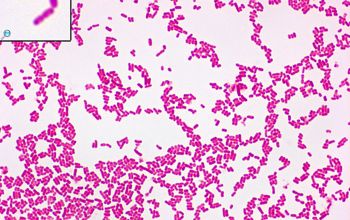

• Gram stain

• Gram negative rods,

1-3 x 0.5 µm, though their size can be impacted by temperature, growth state, and exposure to antibiotics.

They occur singly or in pairs